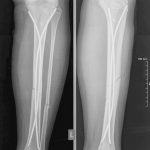

Այս ուսումնասիրությունը հիմնված է 21 հիվանդների (17 տղա, 4 աղջիկ) շարունակական խմբի բուժման արդյունքների վերլուծության վրա, որոնք ենթարկվել են տիտանե էլաստիկ մեխերով վիրահատության։ Հիվանդների տարիքը եղել է 4 տարեկանից մինչև 16 տարեկան։ 9 երեխայի մոտ կոտրվածքի պատճառ է հանդիսացել ձեռքի վրա անկումը, մնացածի մոտ կոտրվածքն առաջացել է վերջույթի ոլորման արդյունքում, վնասվածքի մեխանիզմը եղել է ուղիղ: 19 դեպքերում կոտրվածքները եղել են փակ, իսկ 2 դեպքում՝ բաց։ Ըստ վնասվածքի տեղայնացման՝ դրանք եղել են դիաֆիզար կոտրվածքներ (15 դեպք), պրոքսիմալ մետաֆիզի մակարդակի կոտրվածք (3 դեպք) և հեռավոր մետաֆիզի՝ (3 դեպք): Կոտրվածքային գծի բնույթի համաձայն՝ դիաֆիզային կոտրվածքներից հայտնաբերվել են 6 լայնակի, 4 թեք, 5 պտուտակաձև։ Մի տղայի մոտ (4 տարեկան), որի մոտ առկա էր սրունքի մ/3-ի բաց թեք կոտրվածք տեղաշարժով և մաշկի մինուս հյուսվածքներով, կատարվել է նաև վերքերի առաջնային վիրաբուժական մշակում և կարում՝ ռետինյա արտաթորիչներով։ Սակայն մի քանի շաբաթ անց սկսվել է մաշկի նեկրոզ։ Այդ իսկ կապակցությամբ կատարվել է երկրորդ վիրահատական միջամտությունը։ Կատարվել է մաշկի աուտոտրանսպլանտացիա։ Մաշկի կտորները վերցվել են առողջ ազդրի առաջային մակերեսից: (Նկ 1)